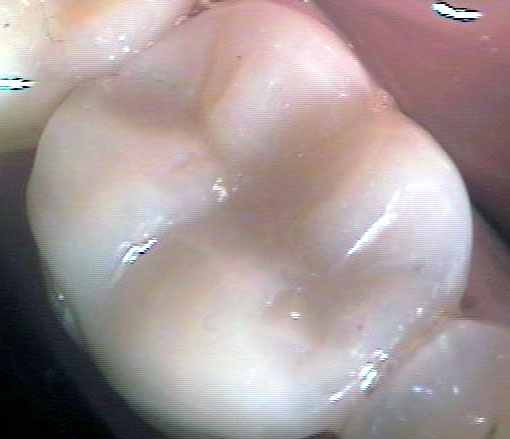

Композитните индиректни възстановявания (т. нар. вставки) са добро решение за възстановяване на кариозни дефекти с по-голям обем. Терминът вставка има руски произход - води началото си от глагола вставлять, който означава поставям. Тъй като през 60-те и 70-те години на ХХ век са се изработвали доста метални вставки, а тогава рускоезичната литература е била най-широко разпространена, е разбираемо защо терминът вставка се използва в българската дентална медицина и до днес. На снимката горе са показани две композитни вставки на зъби 46 и 47. При двата зъба остатъчните странични зъбни стени са били твърде изтънели, което е принудило лекуващия дентален лекар да ги намали на височина. Това се прави с цел вставката да покрие зъба и да го предпази от бъдещо фрактуриране. В този случай цялата дъвкателна повърхност на зъба е изградена от композитен материал.

На снимката горе е показан предишният случай, заснет в по-близък план. Зъботехникът се е постарал да осигури добър оклузален моделаж. Механичната здравина при композитните вставки значително надвишава тази на директните възстановявания. Същевременно керамичните и металните вставки са още по-здрави от композитните. Първенец по отношение на механичната здравина е металната вставка. За съжаление тя е на последно място по естетика - повечето пациенти възприемат крайно негативно металния блясък на този вид конструкции. Тъй като зъботехникът изработва вставката върху гипсов модел, в случая формата на зъба с неговия екватор и контактни точки може да бъде възпроизведена много по-прецизно, отколкото зъболекарят може да извърши при клинични условия. Изработват се изпъкнали и широки екватори, които защитават зъбния венец от механични травми от храната и в същото време изпълват междузъбните амбразури, което предпазва от задържането на хранителни остатъци.